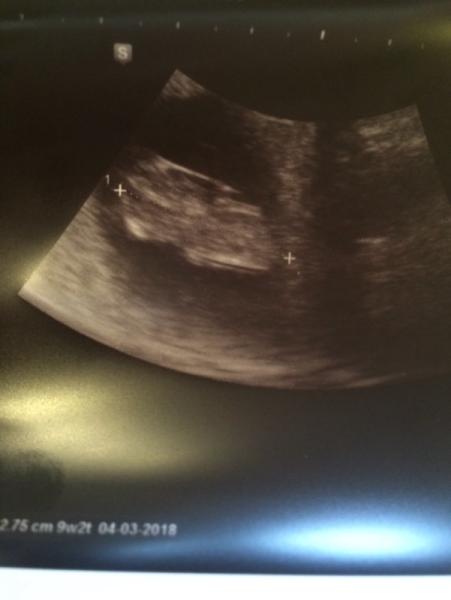

Und hier hat er zwar einen arm, sieht aber aus wie ein gebrochener hühnchenflügel. Vielleicht ist es auch die nabelschnur. Dann hätte er hier auch keine arme und Beine trotzdem ist alles an ihm dran und gesund. Es ist wirklich alles Sache der Perspektive und des Geräts.

Bild zu